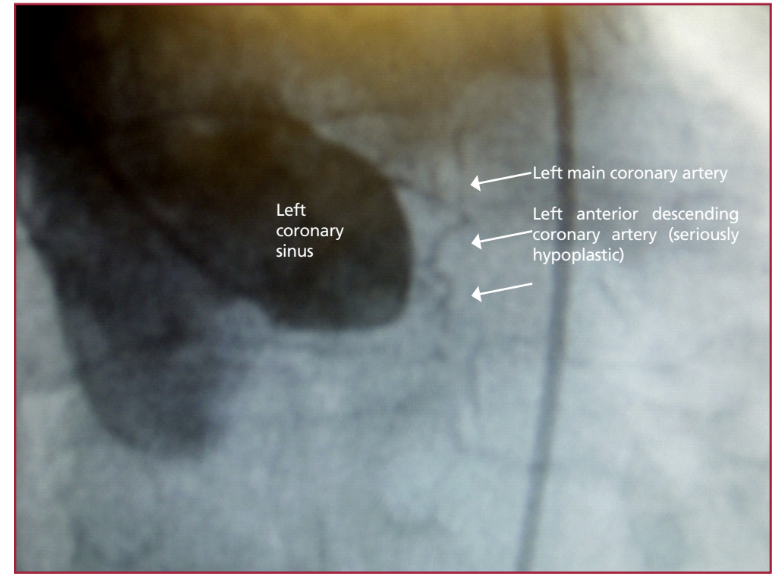

Síndrome coronario agudo secundario a hipoplasia grave del tronco y de la arteria descendente anterior

Las anomalías coronarias congénitas representan una rara entidad que infrecuentemente resulta la etiología subyacente de un síndrome coronario agudo. En esta presentación se describe el caso de una paciente de 48 años portadora de una hipoplasia grave del tronco y de la arteria descendente anterior asociada con un infarto agudo de miocardio sin elevación del segmento ST y se evalúan sus diagnósticos diferenciales, así como la decisión terapéutica. La paciente fue intervenida quirúrgicamente, con una evolución inicial favorable.